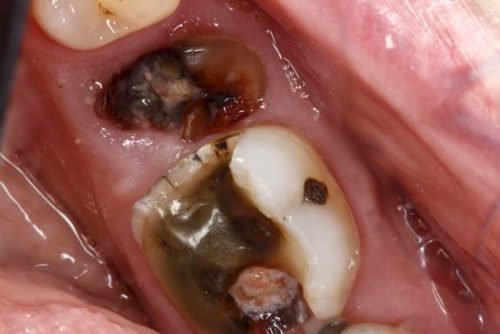

آبسه دندان پری ایپکال یکی از حساس ترین موارد ابتلا به عفونت های دهان و دندان است. چرا که این آبسه دندان خیلی سریع به بافت دندان نفوذ می نماید و در آخر نیز ریشه دندان میکروبی شده و به آبسه مبتلا می گردد. با این توصیف می بایست رفع آبسه دندان پری اپیکال را جدی گرفت. به لحاظ اینکه ریشه دندان به عصب نزدیک بوده و ضمن درگیری شدن یکی از عصب ها، بقیه دندان ها نیز متحمل درد خواهند شد. بنابراین در صورت مشاهده آبسه شدید دندان سریعاً به مطب و کلینیک های دندانپزشکی مراجعه کنید. تا ضمن انجام معاینات و بررسی های دقیق، بهترین روش درمان آبسه دندان برای روی لثه و دندان هایتان انجام شود.

پوسیدگی دندان شایع ترین مشکل اکثر مردم است این پوسیدگی توسط باکتری های معمولی ایجاد می شوند. ذرات غذا تغذیه باکتری ها می باشد و تقریبا 20 دقیقه پس از صرف غذا فرصت دارید تا از تشکیل اسید تولید شده از باکتری ها جلوگیری کنید. ماده تولید شده از باکتری ها به نام پلاک دندان اگر از بین نرود به مرور زمان سخت شده و باعث ایجاد جرم دندان می شود، این جرم دندان علاوه بر عفونت لثه باعث پوسیدگی دندان و سپس دردسرهای بعدی خواهد شد.